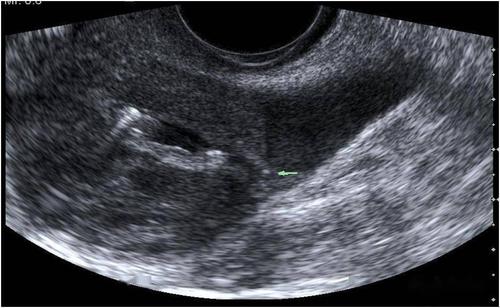

超声典型病例子宫穿孔

超声典型病例:子宫穿孔

子宫穿孔超声表现图

子宫穿孔超声图片

子宫穿孔彩超下表现